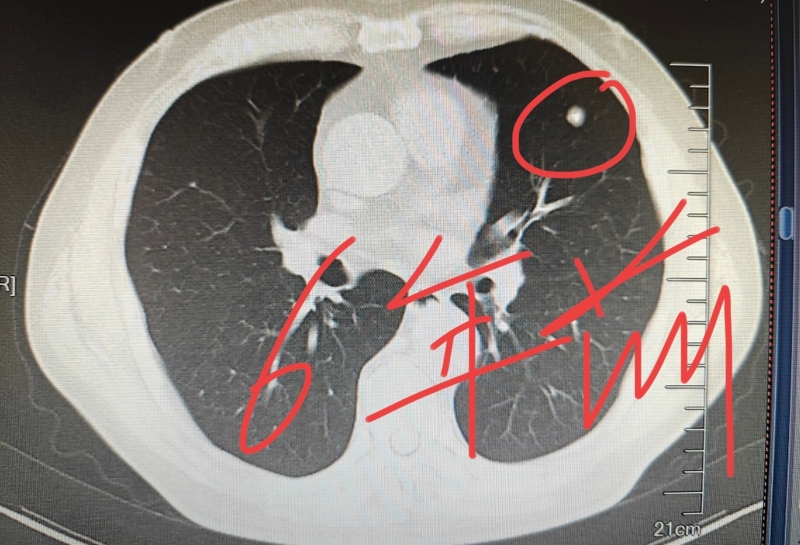

肺腫瘤是一個(gè)中性的詞,它分為良性和惡性兩種,惡性的最常見的就是肺癌。如果考慮是肺癌,除非是那種很小的磨玻璃結(jié)節(jié)型肺癌,生長(zhǎng)速度不快,如果是那種實(shí)性的,直徑大一些的肺癌,生長(zhǎng)速度會(huì)比較快。那如果肺腫瘤是良性的呢,就一定不變嗎?在回答這個(gè)問題之前,我們來看一個(gè)具體的病例。有一位中年女士帶著父親的片子過來找我看病,她父親今年70多歲,在六年前拍胸部CT,發(fā)現(xiàn)了肺里有一個(gè)結(jié)節(jié),直徑一厘米,當(dāng)時(shí)考慮良性的腫瘤,像是一個(gè)錯(cuò)構(gòu)瘤。前兩天,她父親又到醫(yī)院復(fù)查了一下,發(fā)現(xiàn)這個(gè)肺結(jié)節(jié)直徑增大到了15mm。大家從下面的片子里面,可以直觀的看到這個(gè)肺結(jié)節(jié)的變化?,F(xiàn)在雖然增大了,仍然考慮是一個(gè)錯(cuò)構(gòu)瘤,這是一個(gè)良性的腫瘤。通過這個(gè)病例我們可以知道,肺部良性腫瘤也會(huì)逐漸增大,只不過生長(zhǎng)的速度要比惡性的慢。